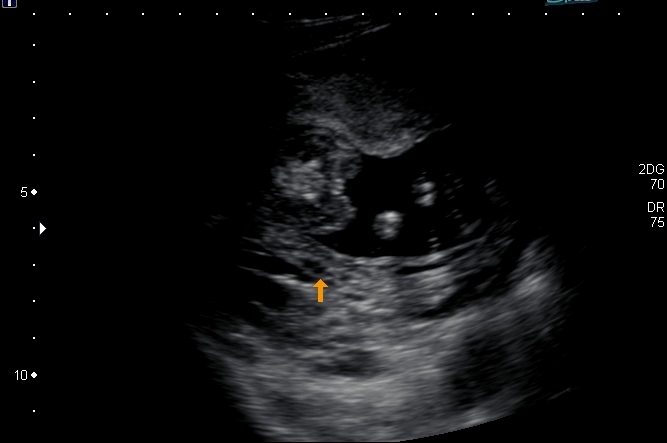

12 weeks 4 days nub

Attachment 14223